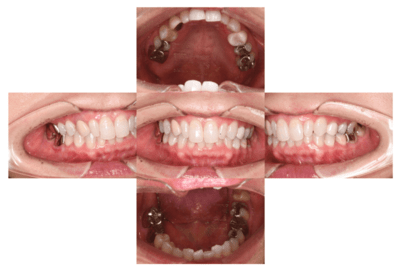

初診時の口腔内

説明:

初診時の口腔内です。かぶせ物があり、一見虫歯とはわからないです。

初診時のパノラマレントゲン

初診時のパノラマレントゲンです。右上の歯が虫歯によって大きく欠けているのがわかります。

歯が大きく欠けた

歯ぐきが治癒した

右上の歯が大きく欠けています。黒く虫歯になっているのがわかります。移植を計画しましたので、歯ぐきがしっかり治癒するのを(1ヶ月)待ちました。

2022.7.9 経過観察後

口腔内写真